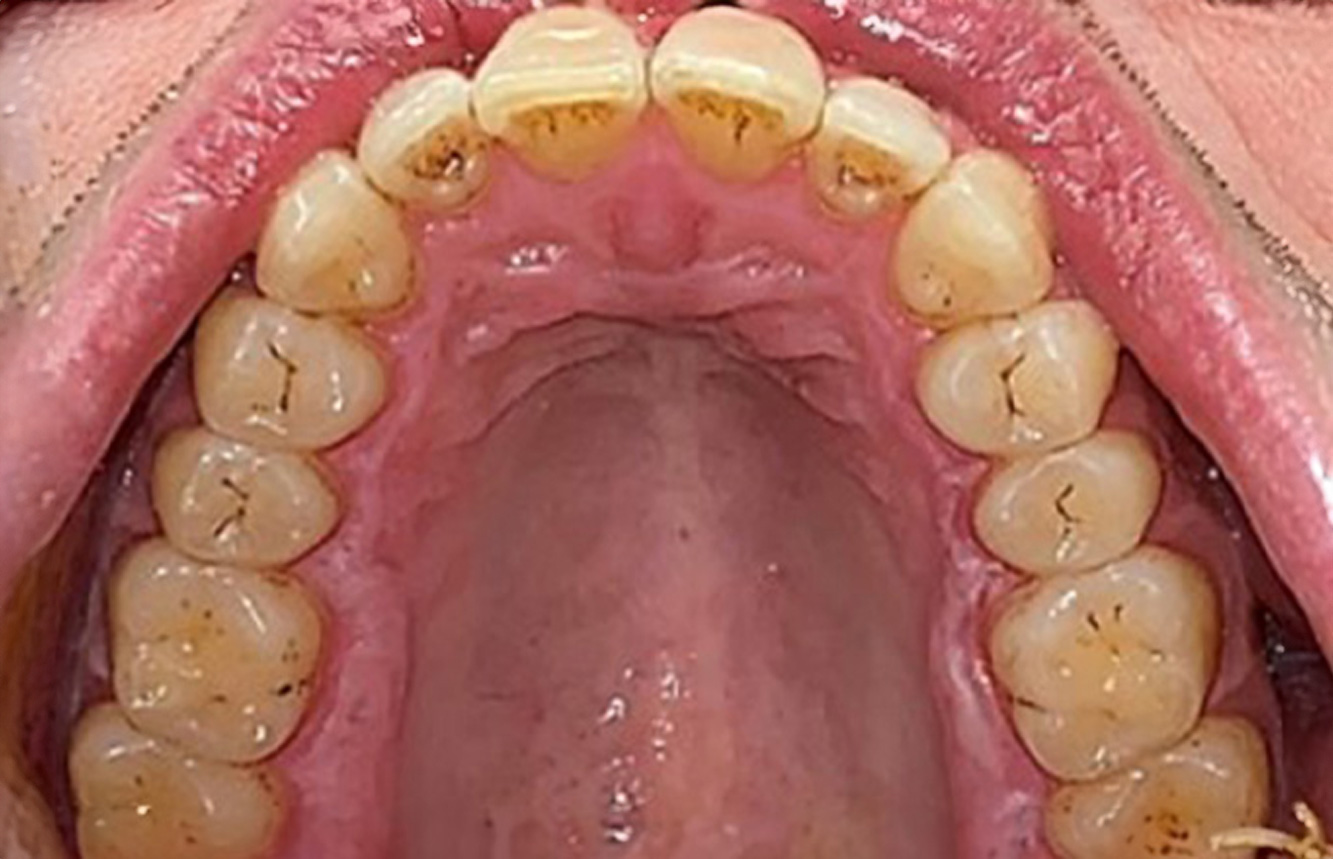

Patient cases according to IPC

The following case studies* serve to illustrate the interaction between the need and risk factors defined for the IPC, as well as the effects of individual factors.

The healthy patient with pre-existing periodontal disease & peri-implantitis

A 52-year-old patient presents at a preventive care session. The patient has no systemic disease and is not taking any medication. He has had various dental treatments and also has two active carious lesions. In addition, the patient has four implants (2nd, 3rd and 4th quadrants). He is revealed to have early periodontal disease (stage IV, grade B). His periodontal condition is stable; a probing depth of Probing depths (ST) of 5 mm is only evident at the implant in region 36. Gingivitis is also identified. more